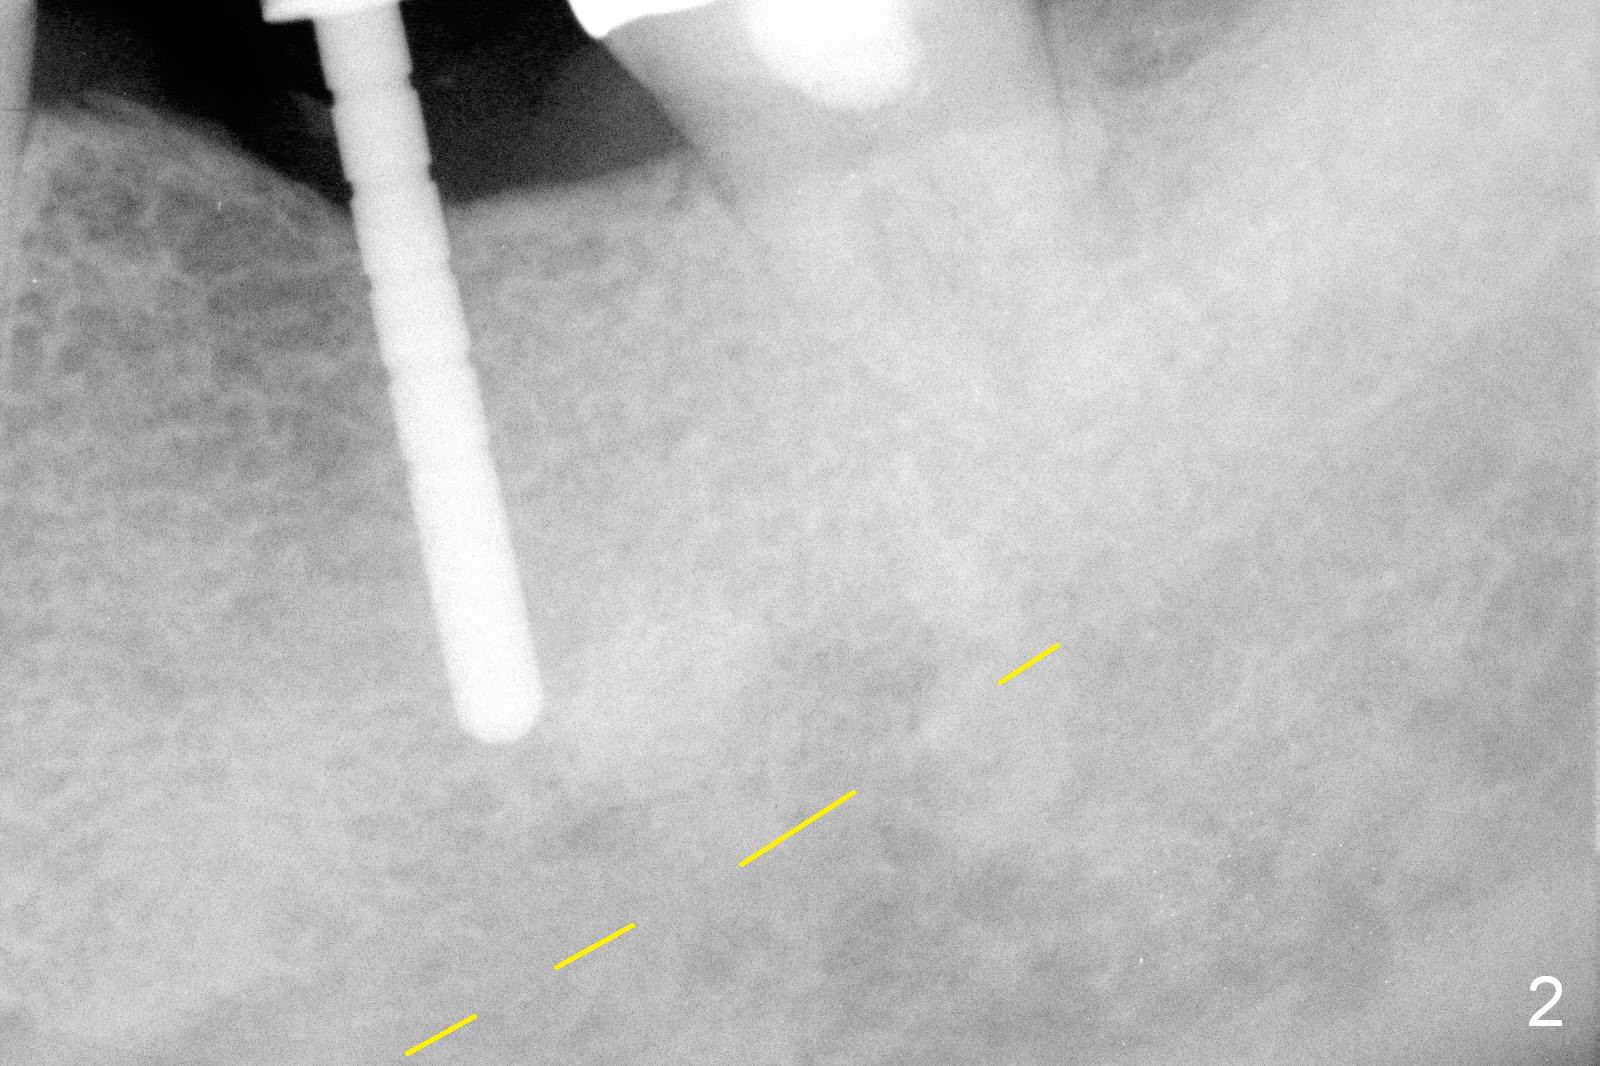

It appears that the diameter of the implant should be also controlled. A smaller implant may not lead to thread exposure and ultimately bone loss. It remains to be true 7 months post cementation (Fig.5). It appears that a 4.5 mm implant is better choice. There is no sign of periimplantitis. Oral hygiene, soft and hard tissues remains basically the same 2 years post cementation (Fig.6). The mesial open margin may be related to failure of impression material to get to the margin in spite of laser gingivectomy.